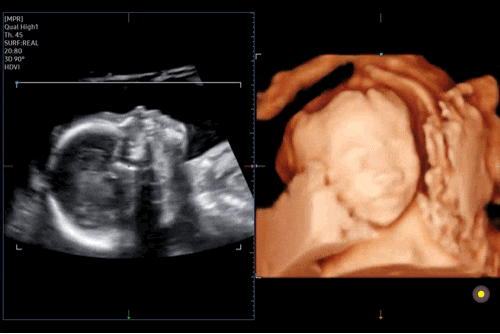

임신 20w2d / 중기 정밀초음파, 입체초음파, 전원 준비 끝 / 창원한마음병원

2024. 09. 13 (금) 8시 30분 채혈 9시 진료 예약 9시 05분 초음파실 진료 10시 교수님 진료 드디어 기다리...